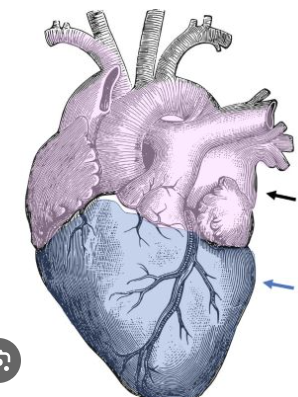

Which blood vessels are typically depicted as blue?

Veins

Which blood vessels are typically depicted as red?

arteries

Unlike the rest of the body, what colors depict the pulmonary arteries + veins?

arteries= blue

veins= red

What does the color blue indicate about status of the blood in vessels?

nutrient poor

CO2 dense

O2 deficient

What does the color red indicate about status of the blood in vessels?

nutrient rich

O2 rich

CO2-less

Identify the light purple area?

base of the heart

Identify the dark blue area?

apex of the heart

What side of the body is the majority of the heart positioned in?